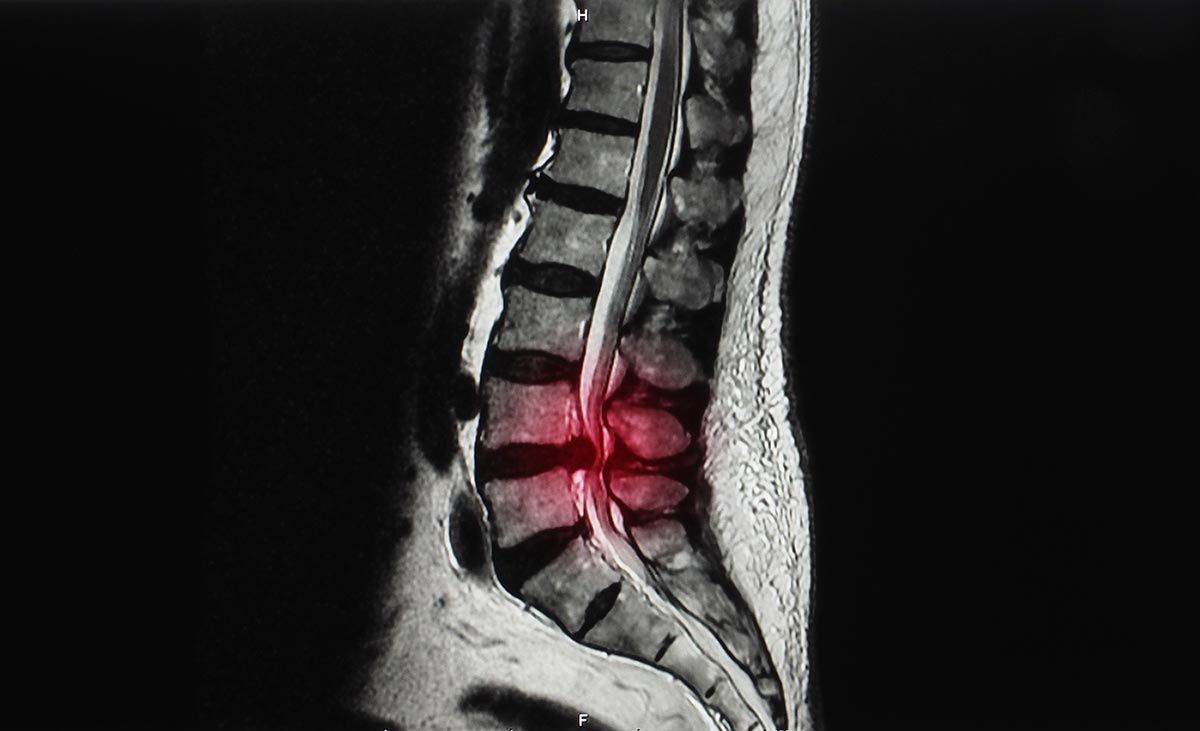

Spinal stenosis happens when the space inside the backbone is too small. This can put pressure on the spinal cord and nerves that travel through the spine. Spinal stenosis occurs most often in the lower back and the neck. Some people with spinal stenosis have no symptoms.